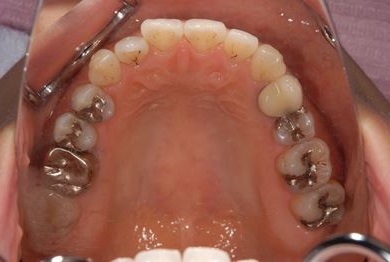

| 性別/年齢 | 女性 / 34歳 | ||||||||||||||||||||||||||||||||

| 主訴 | 以前虫歯を治療して金属を入れたところが、再び虫歯になったのか、軽くしみたり違和感がある。 | ||||||||||||||||||||||||||||||||

| 治療方針 | セラミック治療にて、審美的回復を行う。 | ||||||||||||||||||||||||||||||||

| 治療内容 | メタルボンドセラミッククラウン1本(メタルボンド用土台1本) | ||||||||||||||||||||||||||||||||

| 総治療費 | 125,685円 | ||||||||||||||||||||||||||||||||

| 治療期間 | 3ヶ月 |